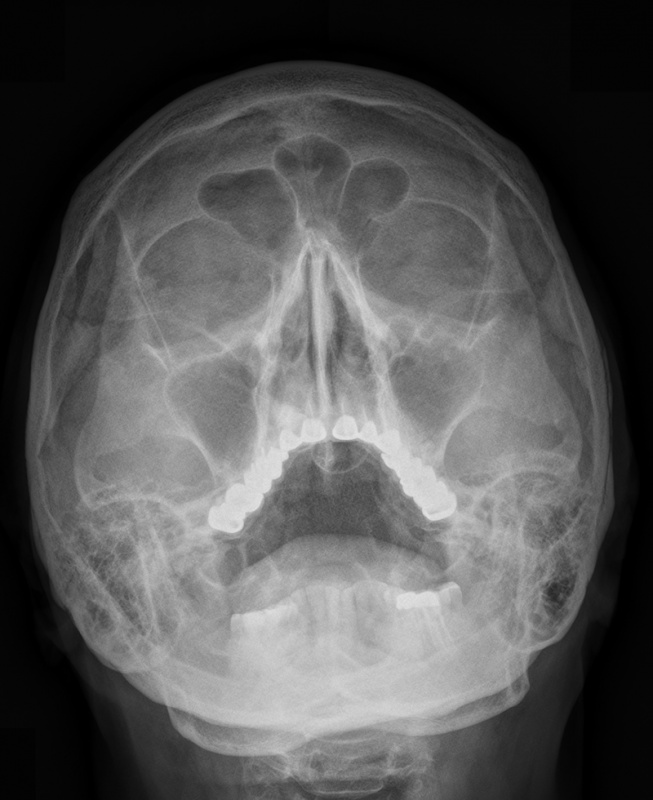

Рентген – метод исследования, который давно и прочно занял свое место в диагностике различных заболеваний. Его суть заключается в облучении определенного участка тела рентгеновскими лучами, в результате чего на снимке визуализируется проекция органа в черно-белом цвете.

С помощью данного метода можно увидеть различные новообразования, последствия травм, полипы, а также оценить успех лечебных мероприятий. В ЛОР-практике рентген повсеместно используют для исследования пазух носа.

Как правило, снимки пазух делают в нескольких проекциях:

• подбородочной;

• носоподбородочной.

Это дает возможность провести визуализацию всех участков и структур носоглотки и подтвердить факт развития патологического состояния. Также, рентгенологическое исследование помогает определить аномалии развития и строения лицевых костей, хрящевой ткани, размер их повреждений.

С помощью снимка врач видит, есть ли жидкость в пазухах, какой ее объем и локализация. Рентген носа является быстрым и информативным способом определить расположение посторонних предметов, а также решить, как лучше их извлечь.